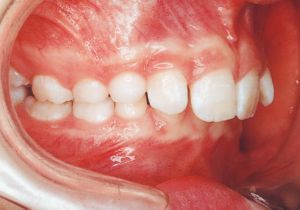

Age at Initial Visit: 11years 3month, Male / Deep bite. Protruding upper bite, Spaced arch.

1 Initial Visit 9-3-’91

Class II deep bite in mixed dentition. A significantly large overjet and a spaced arch are observed. The cephalometric X-ray shows that the anteroposterior displacement of the maxilla and mandible is not particularly large (ANB 5°), but the nasal floor is elevated anteriorly, providing evidence supporting a history of thumb sucking. The skeletal form shows a relatively slight mandibular body deficiency, but the mandibular ramus is adequately sized and appears likely to develop sufficiently. The use of headgear was planned to suppress maxillary anterior growth and achieve relative mandibular advancement. Treatment was performed without extraction, assuming continuity until the permanent dentition stage.